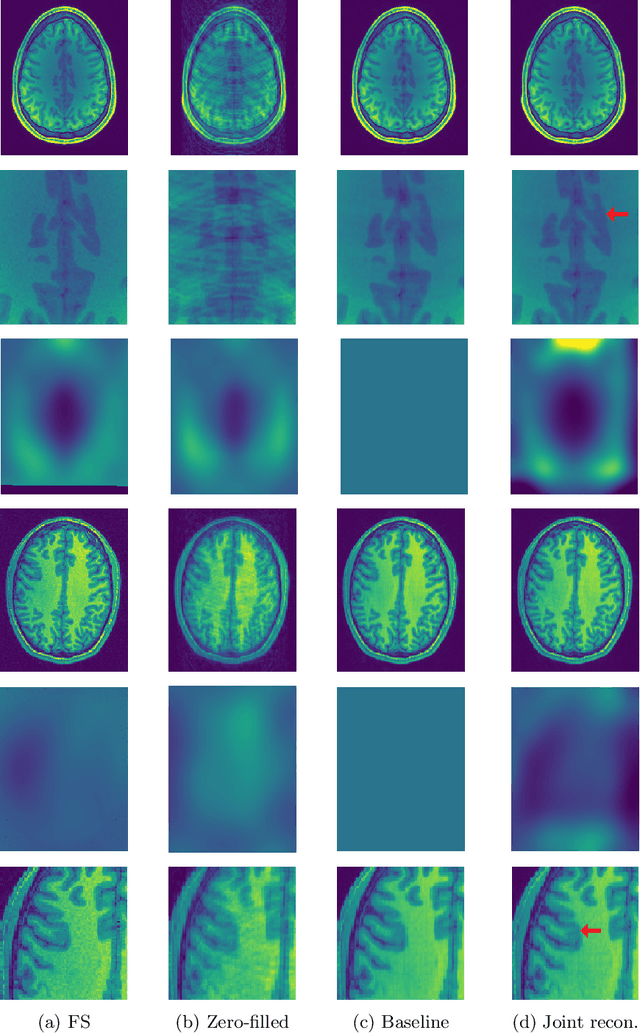

Abstract:Undersampling the k-space in MRI allows saving precious acquisition time, yet results in an ill-posed inversion problem. Recently, many deep learning techniques have been developed, addressing this issue of recovering the fully sampled MR image from the undersampled data. However, these learning based schemes are susceptible to differences between the training data and the image to be reconstructed at test time. One such difference can be attributed to the bias field present in MR images, caused by field inhomogeneities and coil sensitivities. In this work, we address the sensitivity of the reconstruction problem to the bias field and propose to model it explicitly in the reconstruction, in order to decrease this sensitivity. To this end, we use an unsupervised learning based reconstruction algorithm as our basis and combine it with a N4-based bias field estimation method, in a joint optimization scheme. We use the HCP dataset as well as in-house measured images for the evaluations. We show that the proposed method improves the reconstruction quality, both visually and in terms of RMSE.